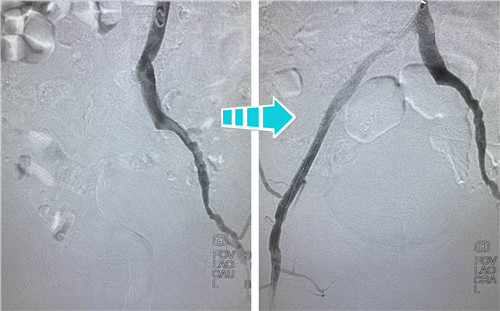

身經(jīng)百戰(zhàn)的放射科介入團隊,在南京鼓樓醫(yī)院血管外科王煒教授的指導(dǎo)下,決定為吳老先生行兩側(cè)髂血管成形術(shù)。手術(shù)當(dāng)天,選擇經(jīng)左側(cè)肱動脈入路,置入90CM長鞘,在導(dǎo)絲指引下,小心翼翼地通過左側(cè)股總動脈狹窄段,給予球囊擴張,精確定位并植入支架,左側(cè)髂血管就此打通。考慮后期患者情況改善,可能還需要處理股淺動脈,專家們還預(yù)保留了股淺和股深開口。